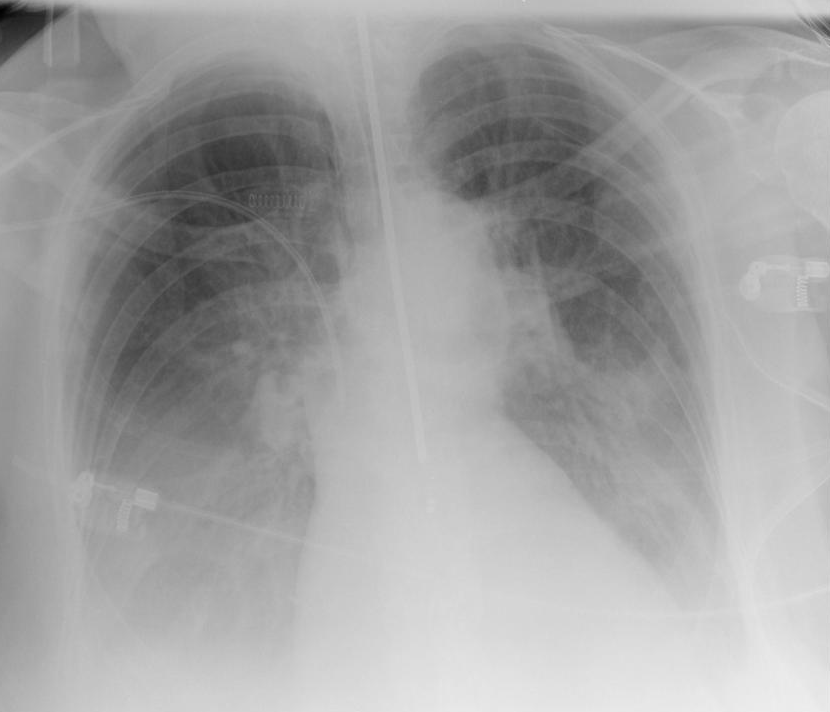

Diagnostic Imaging: CXR systematic approachs

Use a systematic approach

• Airway Structures

Trachea, Carina, Bronchi

• Breathing Structures

Lungs, Pleura

• Cardiac

Heart size, borders

• Diaphragm

Costophrenic angles

• Everything else

Aorta, bones, tissue